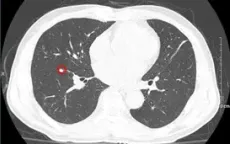

VTV.vn - Nhờ duy trì khám sức khỏe định kỳ, người bệnh 70 tuổi phát hiện ung thư phổi giai đoạn sớm và được phẫu thuật thành công tại Bệnh viện K, phục hồi nhanh sau mổ.

VTV.vn - Ung thư phổi là bệnh lý ung thư gây tử vong hàng đầu nhưng nếu phát hiện ở giai đoạn sớm, người bệnh có thể điều trị khỏi bằng phẫu thuật, không cần hóa xạ trị.

VTV.vn - 75% người mắc ung thư phổi được phát hiện là ở giai đoạn muộn, tỷ lệ tử vong cao. Tầm soát ung thư sớm sẽ tăng khả năng sống và giảm gánh nặng chi phí.